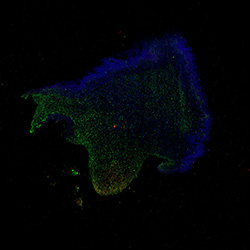

11PCW

Merged

11PCW human midbrain